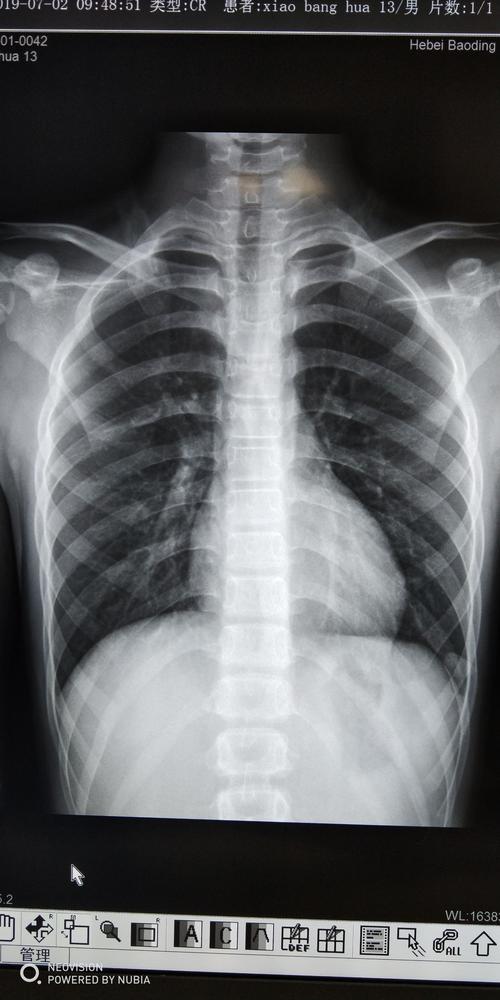

6步法从胸片进行胸部评估

来,我教你看胸片!

胸片怎么看

肺炎胸片